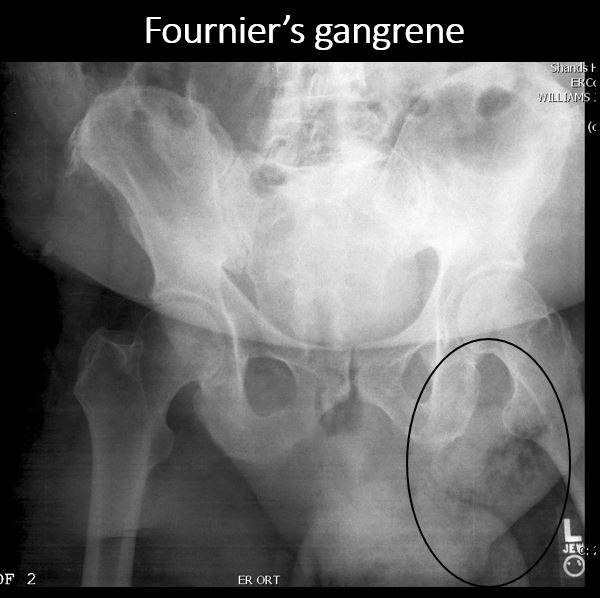

There is air or a foreign body in the extra- abdominal soft tissues of the abdomen, pelvis, or perineum. |

No | NA |